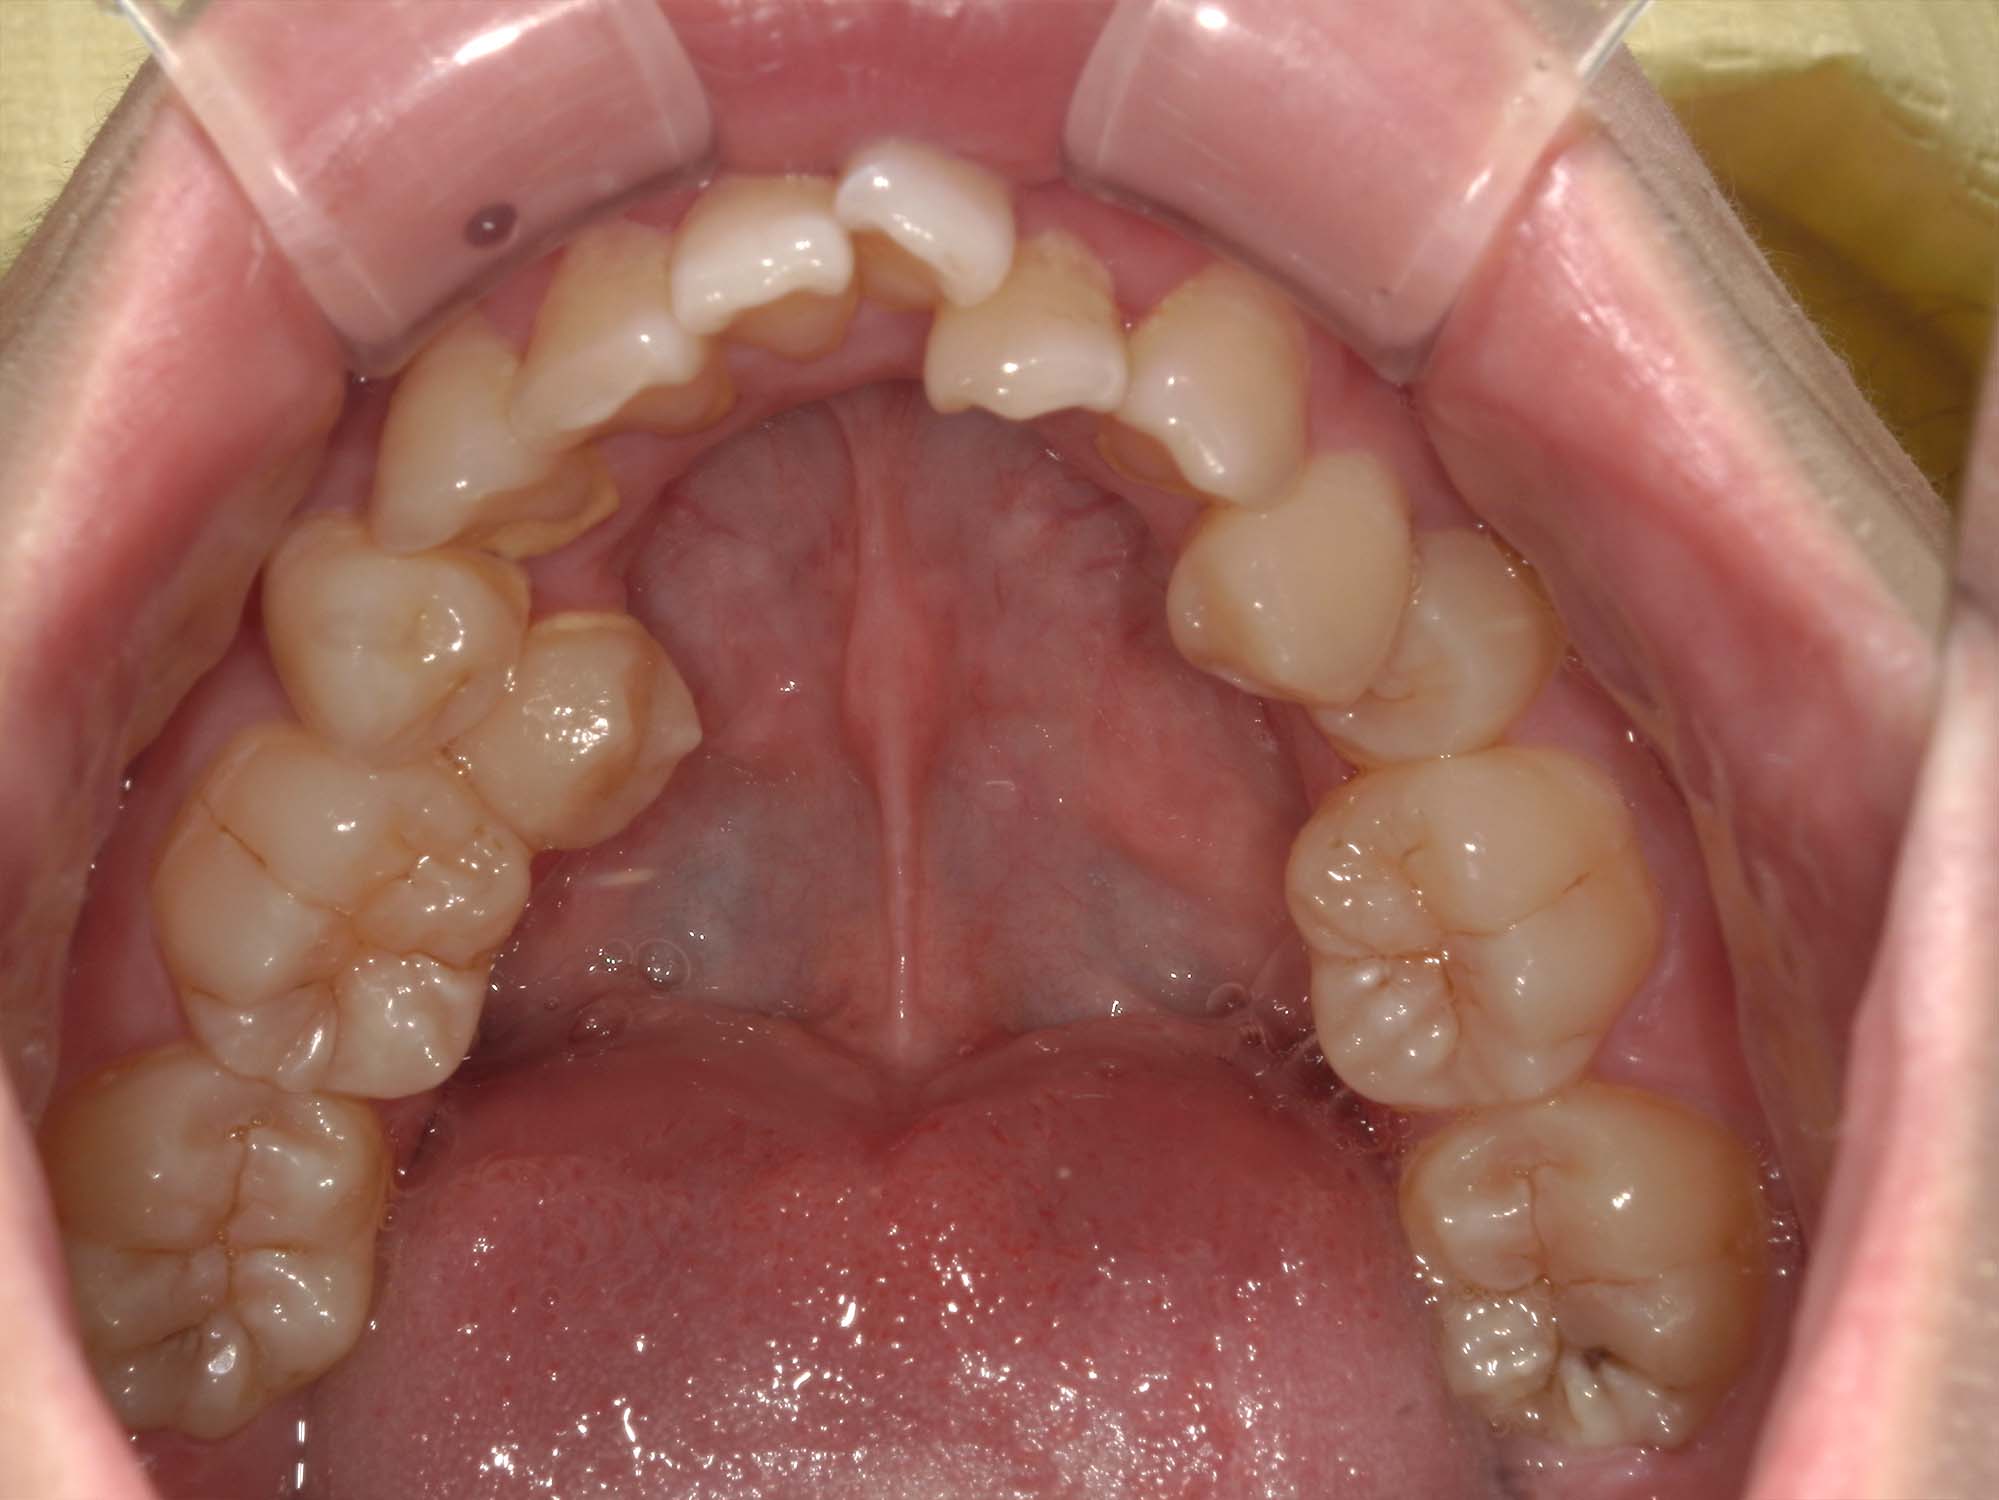

| 年齢・性別 | 21歳 |

|---|---|

| 主訴 | 叢生が気になる・前歯に埋伏歯がある |

| 治療期間・回数 | 6ヶ月 |

| 費用 | 935,000円 |

| 上顎の左側3番が埋伏していたため、上顎左右の3番および親知らずを抜歯し、矯正治療を行いました。 治療開始からおよそ6ヶ月で歯列が整い、審美的にも機能的にも良好な結果が得られた症例です。 |